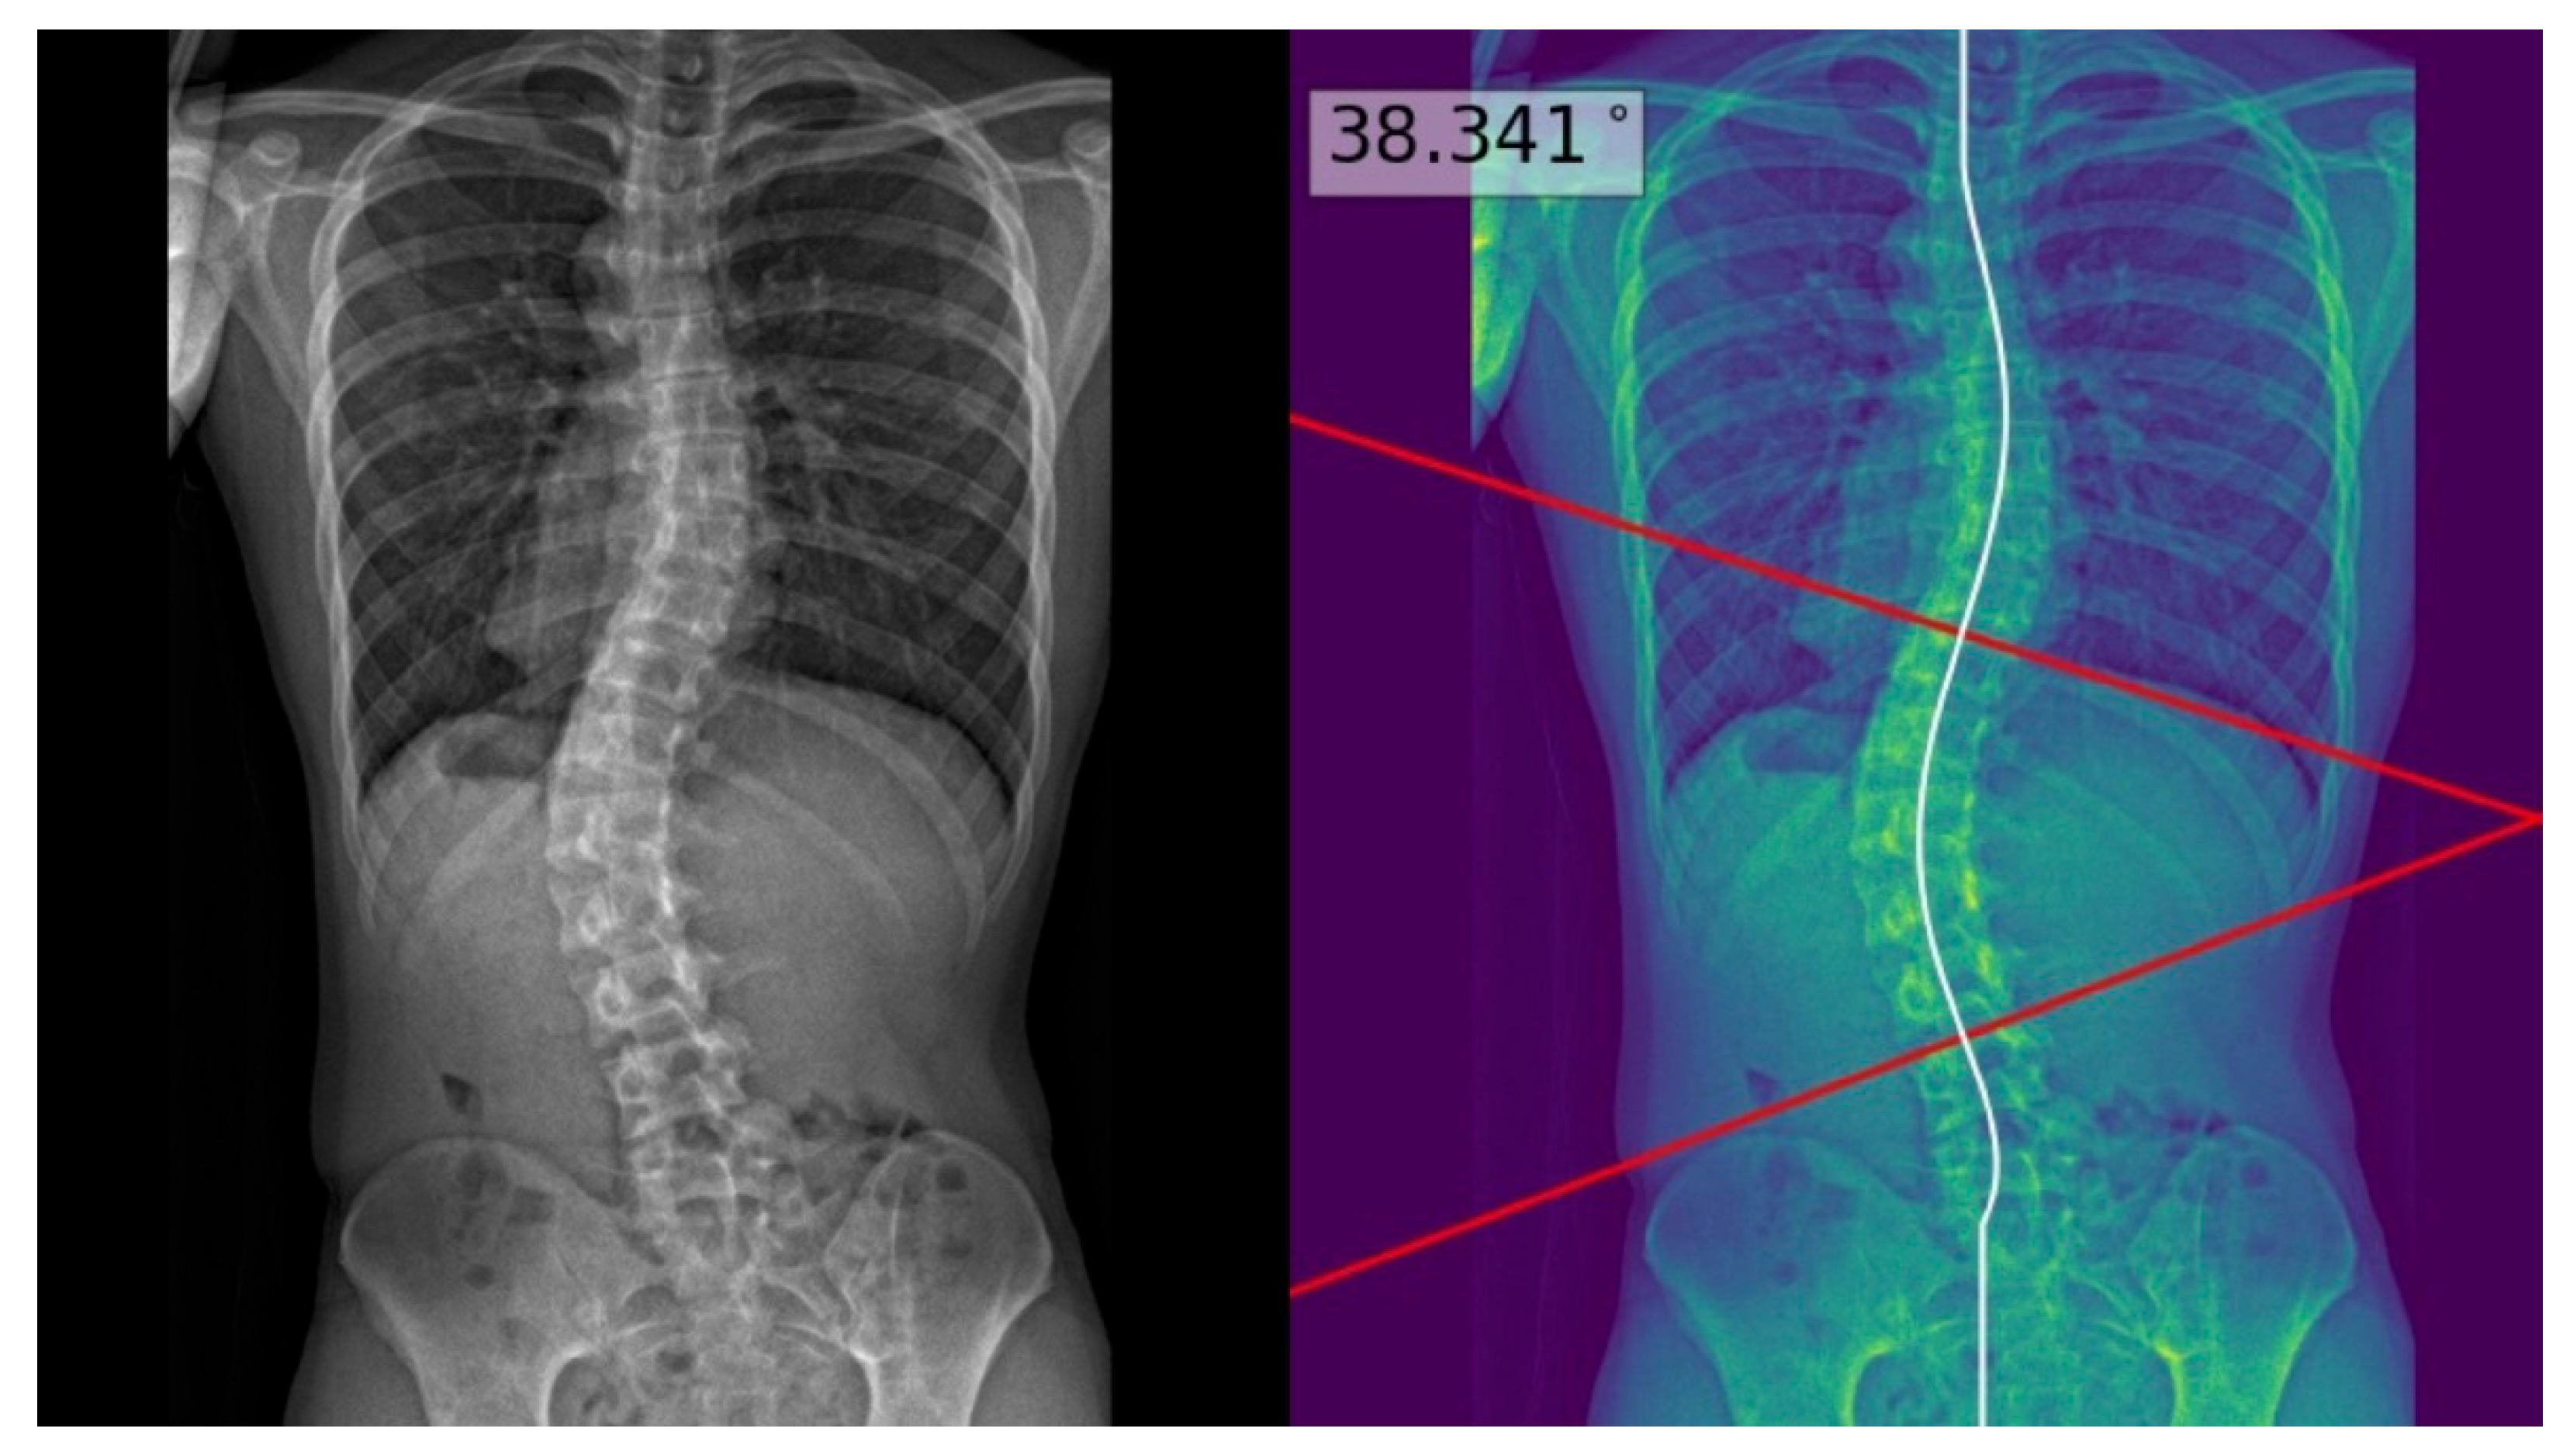

The process above allowed deep learning model masks of the whole spine (showing individual vertebrae) to be obtained and compared to the manual annotations. The model achieved a Dice similarity coefficient of 0.88 and Intersection over Union (IOU) of 84% on validation; it achieved a Dice coefficient of 0.619 and IOU of 72% on testing. Using the masks, the deep learning model determined the center of each vertebra, and extrapolated a polynomial curve along the centers. The spline technique, or the exhaustive assessment of the maximum angles between the vertebrae center line pairs to determine the largest angle, was the method of choice for the measurement of Cobb’s angle. Once the model has identified the correct points on the line, the reader could view the model prediction as extended lines and text in the top right hand corner of the image. For physicians’ review and augmentation, the model (available at the following web server: https://radweb.sha.endeavour-poc.ai/, accessed on 1 May 2022) annotated the largest possible angle in the output images, as shown in Figure 2 and Figure 3. Appendix A provides more details on the deep learning model.

The readers performed manual measurements of the major coronal curve angle without assistance from the deep learning model using the digital angle tool on the Picture Archiving and Communication System (PACS) (Centricity, GE Healthcare, Chicago, IL, USA), with the results overlaid on the images. When interpreting the radiographs with assistance from the deep learning model, the readers accessed the automated major coronal curve calculations and annotations overlaid on the images (as illustrated in Figure 2 and Figure 3). The readers could accept the model predictions or perform manual calculations using the same digital tool as per their clinical judgment, especially if the center curve alignment did not match the image.

Figure 3. Posteroanterior whole-spine radiograph for scoliosis assessment (left) with the deep learning model polynomial curve (fitted to the centers of the vertebrae) and Cobb’s angle prediction overlaid on the image (right). This is an example of a poor model prediction as it was not fitted to the inferior curve, with more than 10 degrees of difference from the reference standard Cobb’s angle.